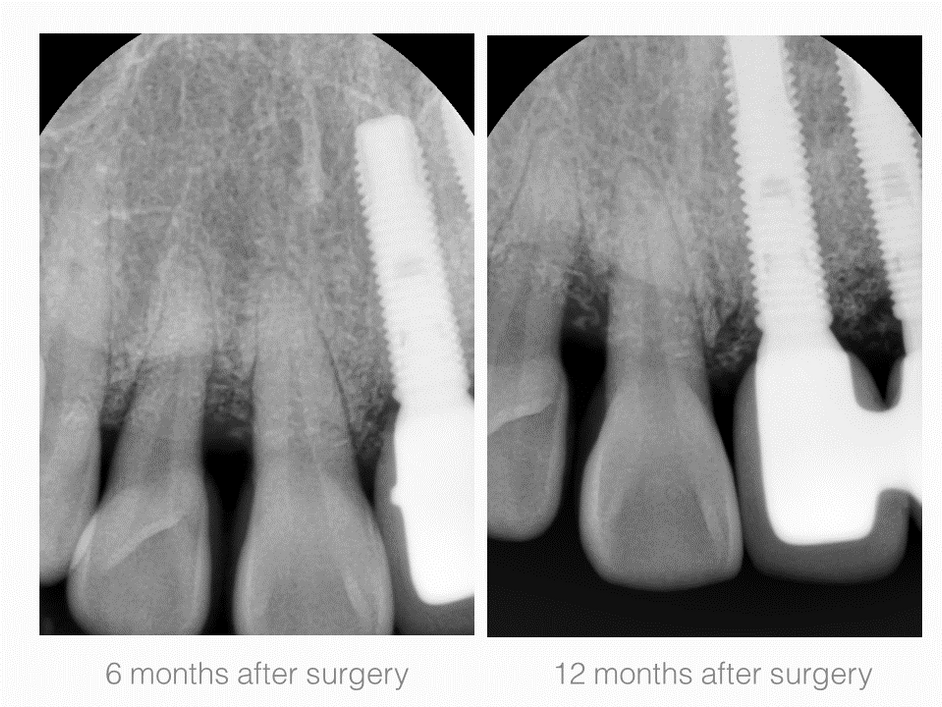

Periodontal Defects

2. Maxillary Lateral incisor